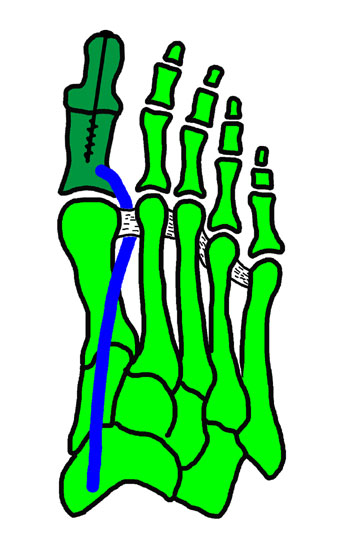

11"> Der Hallux varus Winkel  <a class=11" title="Der Hallux varus Winkel 11" srcset="/assets/images/2/4-vk3bypbg5s5x7zc.jpg 1x, /assets/images/3/4-aax2sd1hrpnrvrb.jpg 1.452x" width="270" height="240" loading="lazy">

Abbildung 3

Die bildgebende Diagnostik hilft bei der Klärung der Ätiologie und des Ausmaßes der Fehlstellung. Hierzu sind Röntgen­aufnahmen im Stand in mindestens zwei Ebenen unter Belastung des Fußes erforderlich. Mit Hilfe der belasteten Röntgenaufnahmen wird der Hallux-varus-Winkel, d. h. den Winkel zwischen der Achse der Grundphalanx der Großzehe und der Achse des ersten Mittelfußknochens bestimmt, sowie etwaige Rotationsfehlstellungen des 1. Strahls verifiziert. Eventuelle knöcherne Fehlanlagen bei kongenitalen Deformitäten können hierdurch ebenfalls verifiziert werden.

Weitere Beurteilungskriterien sind:

• degenerative Veränderungen des MTP I

• Kongruenz des MTP I- Gelenkes

• Form und Stellung des Mittelfußköpfchens I

• Ausprägung der Pseudoexostose.

• PASA-Winkel, d. h. der periphere Artikulationswinkel des Großzehengrundgelenkes.

Zur Klärung der Ätiologie wird der intermetatarsale Winkel zwischen Os metatarsale I und II bestimmt. Ist dieser kleiner als 5° oder gar negativ, ist eine Varusstellung der Großzehe oft die Folge.

Am Röntgenbild des belasteten Fußes bestimmt man die Lage der Sesambeine zum 1. Mittelfußköpfchen.

Anhand der Röntgenaufnahme lassen sich die Folgen einer eventuellen Voroperation bestimmen, wie z. B. die Stellung des ersten Mittelfußköpfchens, des ersten Metatarsale nach Korrekturen der Achse bei einer Hallux-valgus-Operation. Mitunter bestehen Nekrosen des Mittelfußköpfchens oder eine übermässige Resektionen der Pseudoexostose. Auch die Länge des 1. Metatarsale kann von Interesse sein, z. B. nach einer Lapidusarthrodese (Johnson 1994).